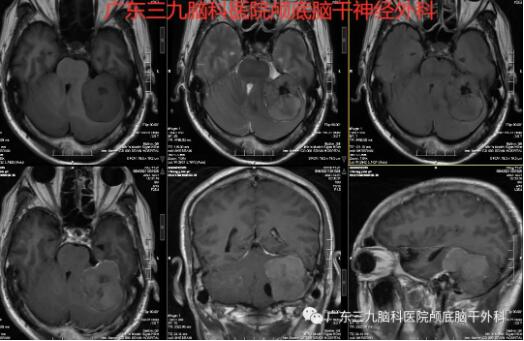

“患者脑膜瘤的位置在后颅窝左侧跨小脑幕上下,大小约49×48×49mm,此部位的脑膜瘤很常见,大部分质地软,容易切除。少部分质地硬,切除困难。”神经外一科主任张良介绍说。

针对患者的病情,神经外一科在科室主任张良的带领下,对患者的身体情况进行全面的术前讨论,制定了详细的手术方案,做好了充分的术前准备。与患者家属充分沟通后,于129号在全麻下行“左侧桥小脑角区脑膜瘤切除术”,术中注意保护后组神经、三叉神经和面瘫神经。整个术程顺利,病理报告示: (右侧桥小脑角)纤维型脑膜瘤,CNSWHO I级。